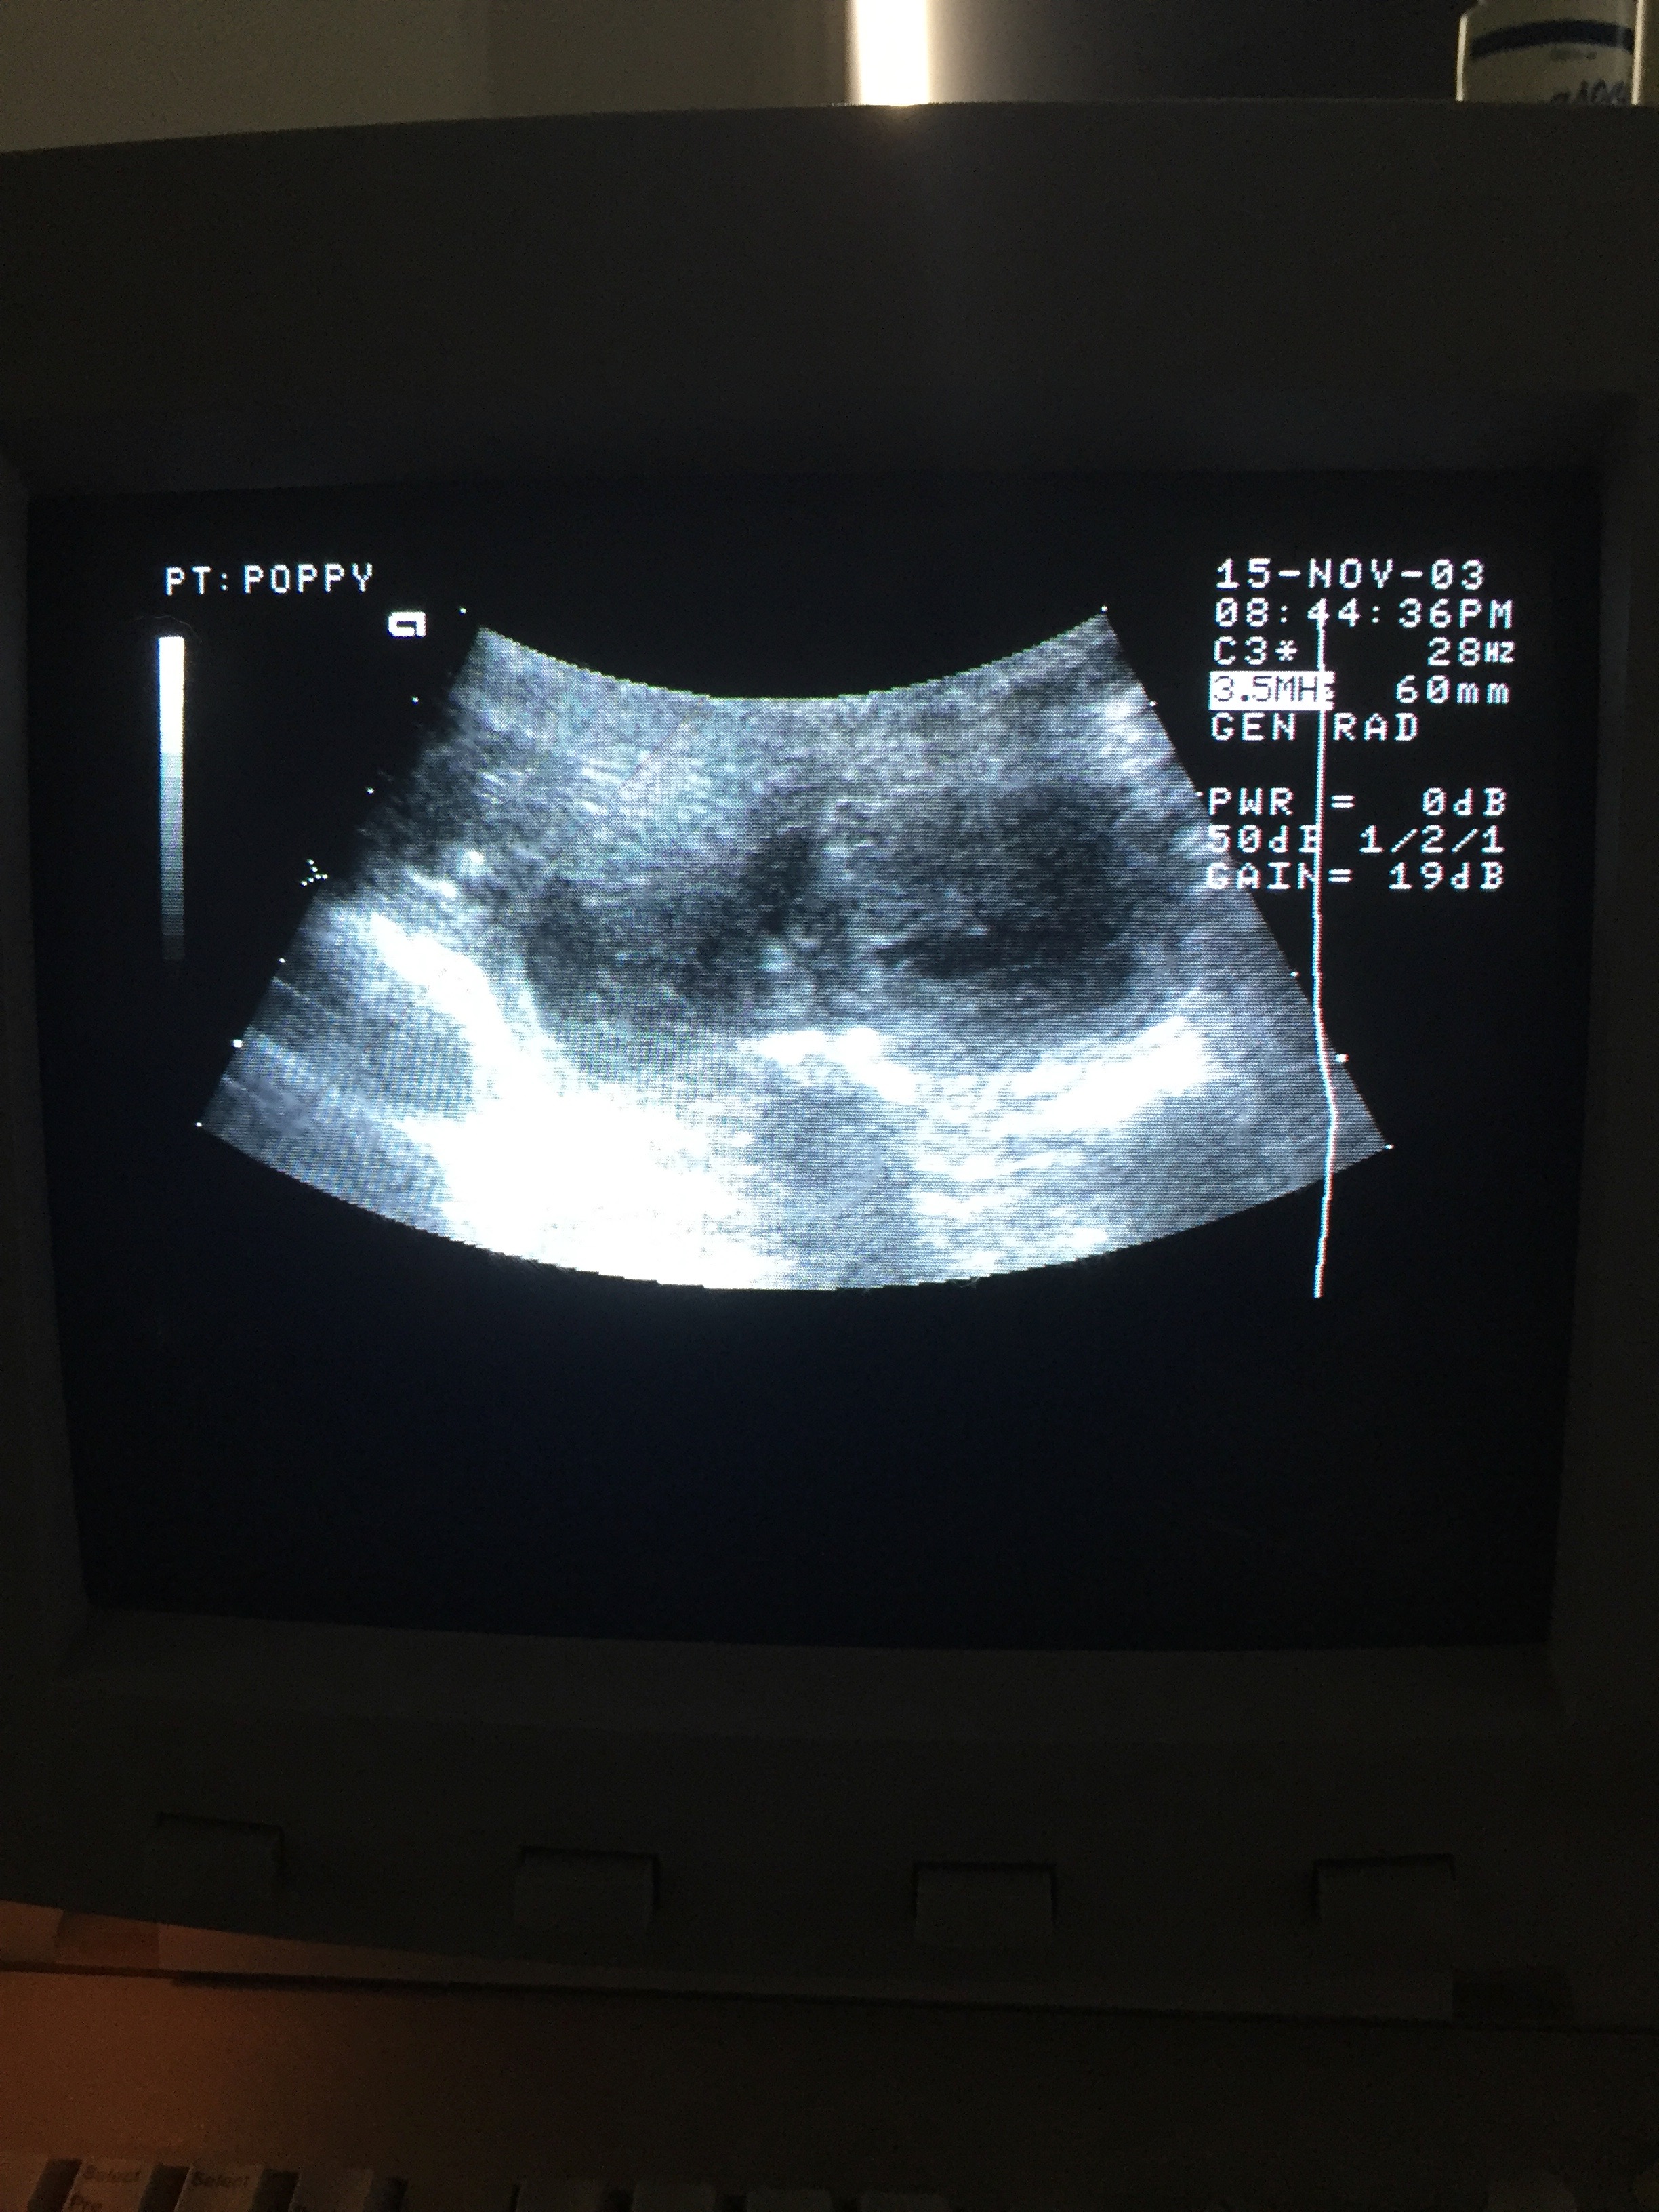

Ultrasound 19 Dec 2018

Poppy’s ultrasound on 19 December 2018. Her appointment was at 9.30am and Dr Bob Cavey of Ultimate Vet Clinic in Narre Warren confirmed her pregnancy. The small marble-like shapes in the centre are puppies! (Note: ignore the dates/times on the image)

19 December 2018 – Day 30

Poppy is now expecting! Bob Cavey counted 5 pups on one side and 4 on the other. There could be more tucked in behind her ribs but it won’t be possible to get a more accurate count until an X-ray at 8 weeks of pregnancy. Based on her progesterone tests in November and likely timing of ovulation, he estimates the due date to be 21 January 2019.